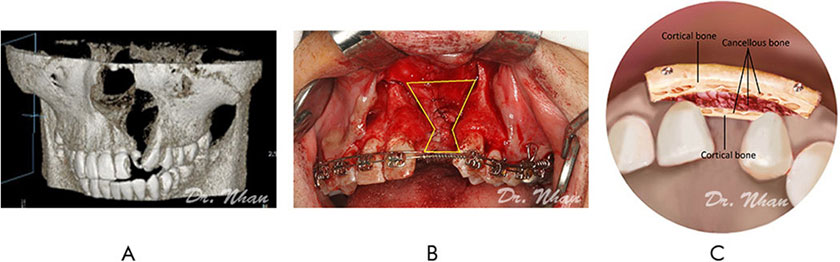

Alveolar bone grafting was performed by the same experienced oral-maxillofacial surgeons. The recipient site was anesthetized by infiltration of lidocaine with 1:200,000 epinephrine. The incision was begun along the cleft margin from the labial to the palate sides. The labial sulcular incision was carried along 2 or 3 adjacent teeth; then, 2 vertical relieving incisions were made and curved (120°) anterosuperiorly at the ends. The palatal sulcular incision was continued to the second premolar, and a vertical releasing incision was made from this area toward the palatal midline, allowing anterior advancement of the palatal attached mucosa (Amin et al., 2002). Full-thickness labial and palatal flaps were reflected. The labial flaps had periosteal releasing incisions, ensuring an adequate nasal lining for watertight closure and sufficient sliding of the flaps. The harvested bone was cut into 2 corticocancellous blocks. The smaller block (palatal block) was shaped to fit the defect margin nasally and inserted against the sutured nasal lining, with the cortical bone layer toward the palatal side (Figure 3A, 3B). The cleft was then nearly filled with harvested particulate cancellous bone.

Figure 3. Bone grafting technique. (A) The alveolar cleft on CT Cone Beam. (B) Size of the alveolar defect (yellow line). (C) The technique of two iliac corticocancellous-block grafting.

The larger block (labial block) was placed on the particulate cancellous bone, with the cortical bone layer toward the labial side and fixed with screws. It covered the radicular bone of the 2 teeth adjacent to the cleft and extended from the alveolar crest to the nasal floor (Figure 3C). During screw fixation, finger pressure was used to protect the palatal flap.